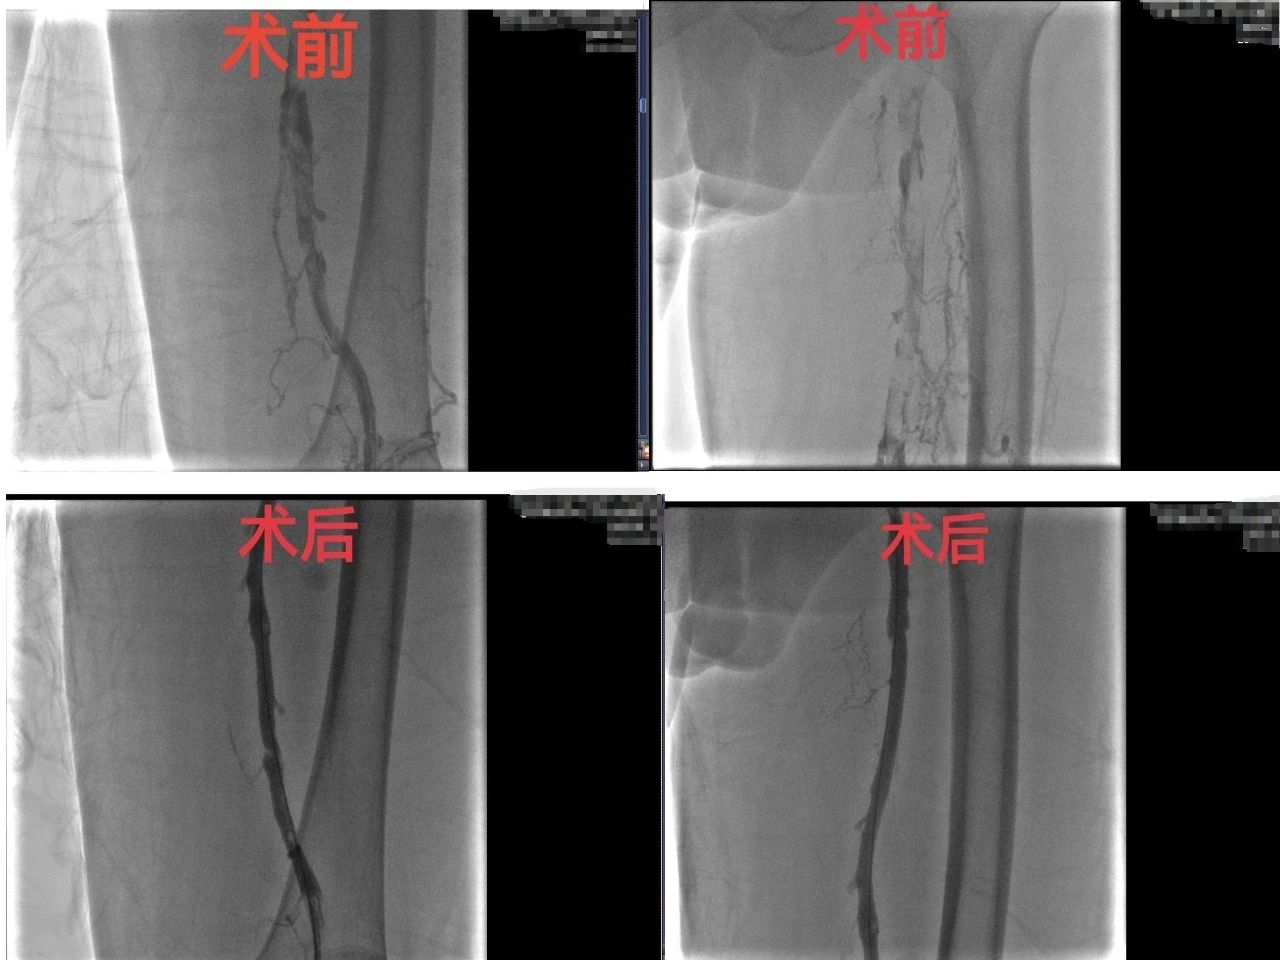

在胡育斌主任医师现场指导下,固原市人民医院肿瘤科介入团队火速启动急诊绿色通道。首先植入下腔静脉滤器,拦截致命血栓,随后运用机械血栓清除系统,高效抽吸左下肢深静脉全程血栓,最后在X光引导下精细开通闭塞血管,恢复血流。三小时后,患者下肢肿胀明显消退,血流通畅,胸闷气短症状缓解,“血管炸弹”成功拆除。术后,患者恢复良好,目前已康复出院。